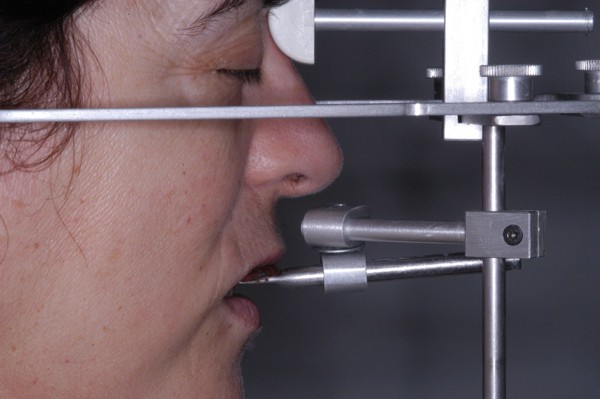

APRECIACIONES DIAGNÓSTICAS EN BASE A LA APERTURA MENTAL DEL CLÍNICO FRENTE A LO QUE EL PACIENTE PROPONE EN MUCHAS OCASIONES , LA DEMANDA DE LOS PACIENTES NOS INCLINAN A FOCALIZAR NUESTRA ATENCIÓN EN LAS PIEZAS DE LAS CUALES EL ENFERMO SE QUEJA. PACIENTE SEXO FEMENINO, 55 AÑOS, SE PRESENTA A LA CONSULTA DERIVADA POR COMPAÑERO GENERALISTA, QUIEN LLEVA MESES PROCEDIENDO A LA «DESINFECCIÓN» DE UN PRIMER PREMOLAR IZQUIERDO, EL QUE SE PRESENTA ABIERTO EN SU CONDUCTO EN EL AFÁN DE PERMITIR EL ESCAPE DE GASES DE UNA GANGRENA PULPAR. A LA INSPECCIÓN CLÍNICA SE OBSERVAN FACETAS PARAFUNCIONALES DE TERCER GRADO , ASINTOMÁTICAS, CON EVIDENTES DIFICULTADES MASTICATORIAS Y ESTÉTICAS , FALTA TOTAL DE SUS MOLARES INFERIORES, Y ADELANTAMIENTO PRONUNCIADO DE SU MANDIBULA, LA QUE CUESTA MANIPULAR DEBIDO A LA SITUACIÓN DE ESPASMO DE CASI TODA SU MUSCULATURA GNATICA. SE ESTUDIA EL CASO RADIOLOGICAMENTE, Y SE RELAJA EL SISTEMA MEDIANTE LAM. DE LONG REALIZANDO UN MONTAJE EN LA ORC OBTENIDA. NO SATISFECHOS CON EL RESULTADO, CONFECCIONAMOS UN JIG DE LUCIA, EL QUE DEJAMOS EN BOCA TODA UNA NOCHE, AL CABO DE LA CUAL REALIZAMOS UN NUEVO REGISTRO REALIZAMOS UN ENCERADO RÁPIDO DEL CASO, Y CONFECCIONAMOS UNA ESTRUCTURA OCLUSAL PLASTICA, QUE ADEMÁS REPONGA EL ASPECTO ESTÉTICO PERDIDO (FÉRULA DE RELAJACIÓN DE COMPONENTE ESTÉTICO), LO QUE PERMITE AL ENFERMO LUEGO DE DOS DÍAS DE USO, NO SOLO CORROBORAR LA COMODIDAD MASTICATORIA Y LA FALTA DE SÍNTOMAS MUSCULARES, SINO TAMBIÉN OBSERVAR APROXIMADAMENTE LA DIFERENCIA ENTRE LA SITUACIÓN INICIAL Y LO QUE PUEDE LOGRARSE MEDIANTE EL TRATAMIENTO. EL PACIENTE ADVIERTE LA MEJORÍA DE LA SITUACIÓN. ACEPTADO POR PARTE DEL MISMO EL TRATAMIENTO SUGERIDO, CREAMOS UN JUEGO COMPLETO DE PROVISORIOS EN BASE AL ENCERADO, Y PROCEDEMOS A TRATAR LA INFRAESTRUCTURA, QUE CONSISTE EN LAS ENDODONCIAS, SUS REFUERZOS A PERNOS DE ORO, LOS ASPECTOS PERIODONTALES DEL CASO, Y DOS IMPLANTES INFERIORES CON TÉCNICA SEMISUMERGIDA ,DE 5 MM DE ANCHO POR 12 DE LONGITUD, CON ANILLO DE ZIRCONIO , A LA ESPERA DE OSTEOINTEGRACIÓN, TRANSCURREN TRES MESES EN EL USO DE UNA NUEVA OCLUSIÓN CONSTITUIDA POR LOS PROVISIONALES, SEGÚN EL ENCERADO, QUE SE REALIZÓ SIGUIENDO LOS CÁNONES DE UNA OCLUSIÓN ORGÁNICA. COMPROBADA LA EFICACIA DE LA NUEVA SITUACIÓN, CON SUS DISCLUSIONES LATERALES Y POSTERO ANTERIORES CORRECTAS, CARECIENDO YA DE SINTOMATOLOGÍA MUSCULAR (SIN MIALGIAS, SIN MIOSITIS, Y CON UN GRADO DE APERTURA DE 4,50 CM), Y SIN SIGNOS EVIDENTES DE DESGASTE SOBRE EL MATERIAL DE LOS PROVISORIOS, ES DECIR: VERIFICANDO QUE EL PACIENTE YA NO BRUXA, VERTICALIZANDO EL CICLO MASTICATORIO /OTORGANDO ORC/ DIMENSIÓN VERTICAL /PROTEGIENDO A LAS PIEZAS `POSTERIORES DE IMPACTOS LATERALES RECIEN ENTONCES , MONTAMOS EN ARTICULADOR SEMI AJUSTABLE LOS MODELOS DE TRABAJO DEFINITIVOS. CONFECCIONAMOS ENTONCES LAS COFIAS INFRA PORCELANA, EN PORCELANA DE ALTA DENSIDAD EN EL SECTOR ANTERIOR Y EN ORO GALVÁNICO PARA EL SECTOR POSTERIOR PARA LUEGO COMPLETAR LA GUIA ANTERIOR , VERIFICANDO LA ALTURA DE LOS INFERIORES RESPECTO DEL LABIO INFERIOR Y CORROBORANDO LOS PUNTOS DE CONTACTOS INTER CANINOS, QUE CENTRALIZAN LA MANDIBULA Y VERTICALIZAN EL CICLO MASTICATORIO Y LAS DISCLUSIONES CANINAS QUE OTORGARÁN PROTECCIÓN A LOS SECTORES POSTERIORES. POSTERIORMENTE CHEQUEAMOS LA DISCLUSIÓN EN PROPULSIVA DE LA GUIA ANTERIOR YA TERMINADA. FIG38 FIG39 UNA VEZ OBTENIDO UN COMANDO ANTERIOR EFECTIVO, COMO LO ES LA GUIA ANTERIOR CON TODOS SUS COMPONENTES, PROCEDEMOS A REALIZAR LAS TABLAS PREMOLAR / MOLAR DE AMBOS LADOS Y OBSERVAMOS QUE LOS PUNTOS INTEROCLUSALES DE CONTACTO SEAN SUFICIENTES Y CUMPLAN SU OBJETIVO DE OTORGAR ESTABILIDAD MESIO DISTAL Y VESTÍBULO LINGUAL. TRANSCURRIDO UN AÑO DE FINALIZADO EL TRATAMIENTO, REALIZAMOS UN CHEQUEO POST OPERATORIO DEL CASO, EN TODOS LOS PARÁMETROS ANTERIORMENTE MENCIONADOS, Y OBSERVAMOS LA ABSOLUTA ESTABILIDAD DEL MISMO EN TODOS SUS NIVELES Y TEJIDOS.